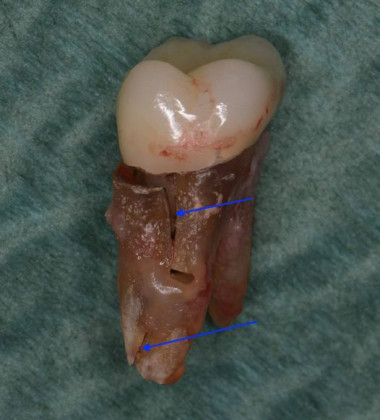

しかし、いくら根管治療が成功しても咬み合わせをきちんと治療しないと画像のように歯が割れてしまいます。(青い矢印部分が歯が割れている部分です)

歯は割れてしまったら抜歯になります。ただでさえ神経の無い歯は免疫が弱いので、割れやすいですからきちんとした咬み合わせのチェックが必要になるのです。名取歯科医院では常に歯の治療はそれだけすればいいわけではなく、全てを診断しチェックすることが大切だと考えています。